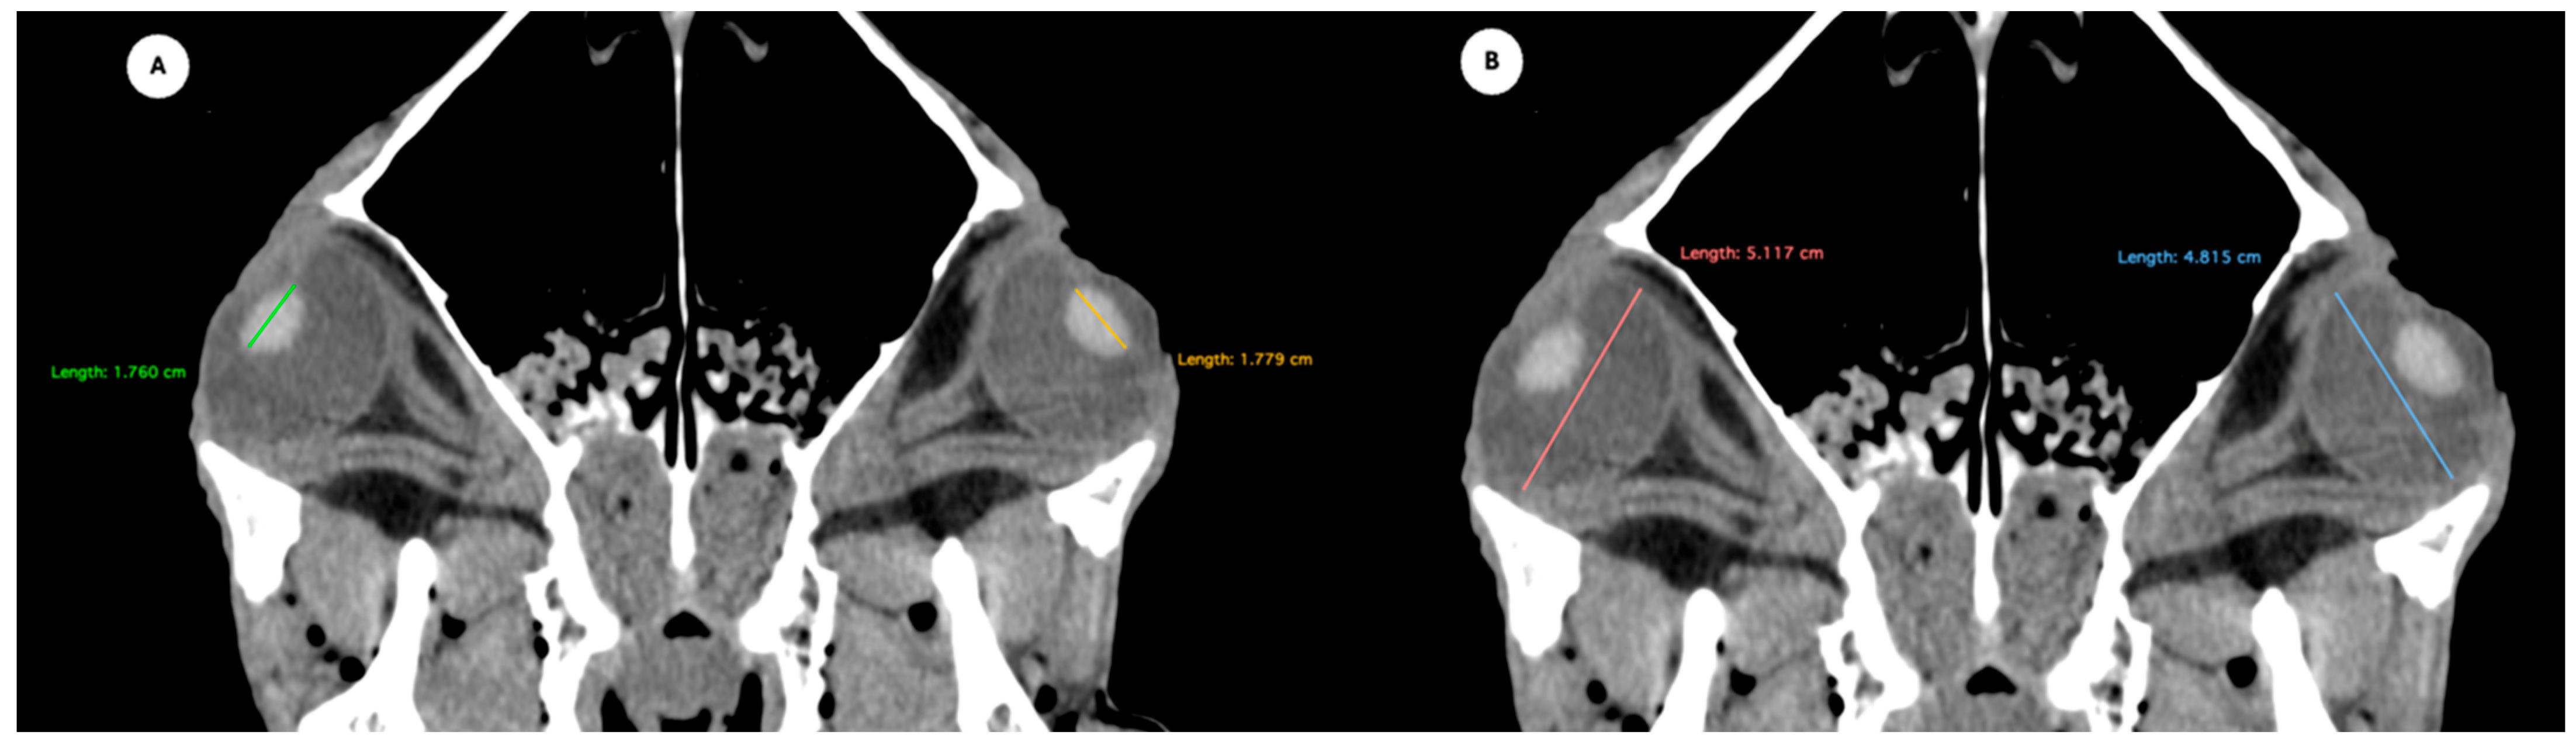

- Anterior and posterior chambers width: Maximal lateromedial distance across the anterior and posterior chambers (Figure 5).

Figure 5.

Transverse multiplanar reconstruction (MPR) image showing the widths of the anterior and posterior chambers, represented by the maximal latero-medial distance across each chamber.

Table 1 provides summary statistics (mean, median, range, and standard deviation) for the internal ocular measurements of the left eye, right eye, and both eyes combined across all 20 horses. The average ocular measurements indicated that the eyeball height (5.19 ± 0.13 cm) was greater than its width (4.28 ± 0.12 cm), confirming the characteristic oval shape of the equine eye. The mean axial length was 5.09 ± 0.17 cm, consistent with previous descriptions of large-globe morphology in horses. The orbital cavity measured 5.27 ± 0.12 cm in height and 6.29 ± 0.14 cm in length. The anterior and posterior chambers had mean widths of 0.56 ± 0.07 cm and 2.26 ± 0.09 cm, respectively. The lens exhibited a mean height of 1.53 ± 0.06 cm, width of 1.23 ± 0.06 cm, and length of 1.63 ± 0.04 cm. These results collectively reflect the regular proportions and bilateral symmetry of the equine eyeball and its internal structures, as detailed in Table 1. The Mann–Whitney U test revealed no statistically significant differences in the measurements between the right and left eyes. Similarly, when all variables were considered collectively, the analysis confirmed the absence of significant differences between both eyes

All eyeball measurements were intercorrelated. Weak correlations were observed between length and width (ρ = 0.329; p = 0.033) and between length and height (ρ = 0.371; p = 0.015). A strong correlation was found between width and height (ρ = 0.704; p < 0.001). Orbital cavity height and length were significantly correlated (ρ = 0.639; p < 0.001), indicating a strong association. Orbital cavity height also showed significant correlations with all eyeball measurements: width (ρ = 0.360; p = 0.019), height (ρ = 0.419; p = 0.006), and length (ρ = 0.542; p < 0.001). In contrast, orbital cavity length was only correlated with eyeball length (ρ = 0.422; p = 0.005). Lens dimensions showed varying degrees of correlation. A strong correlation was found between lens height and lens width (ρ = 0.788; p < 0.001), while a weak correlation was observed between lens height and lens length (ρ = 0.306; p = 0.048). No significant correlation was found between lens width and lens length (ρ = 0.279; p = 0.074). Lens width demonstrated moderate-to-weak correlations with several eyeball and orbital cavity measurements: eyeball width (ρ = 0.346; p = 0.025), eyeball height (ρ = 0.332; p = 0.032), eyeball length (ρ = 0.523; p < 0.001), orbital cavity height (ρ = 0.349; p = 0.023), and orbital cavity length (ρ = 0.484; p = 0.001). Lens height showed moderate correlations with eyeball length (ρ = 0.538; p < 0.001), orbital cavity height (ρ = 0.435; p = 0.004), and orbital cavity length (ρ = 0.539; p < 0.001). Conversely, lens length was not significantly correlated with any eyeball or orbital cavity measurements. Finally, the widths of the posterior and anterior chambers were moderately correlated (ρ = 0.580; p < 0.001). Both variables showed weak to moderate correlations with all eyeball, orbital cavity, and lens dimensions (ρ = 0.337–0.650; p = 0.029 to <0.001), except for the posterior chamber width with eyeball length (ρ = 0.232; p = 0.140), and the anterior chamber width with lens length (ρ = 0.204; p = 0.195), which were not statistically significant.